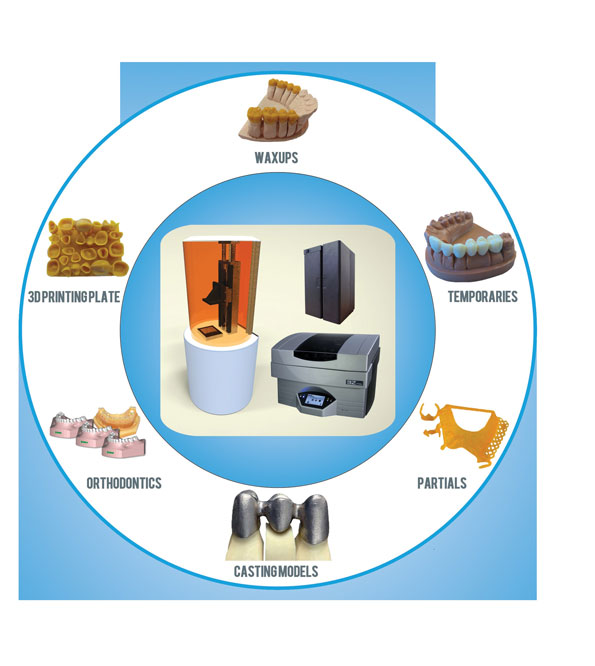

بعد از دیچ کردن دای ها Frame Work مورد نظر را به چهار طریق می توان ساخت :

- وکس آپ دستی که معمولا با استفاده از دیپینگ پات و اسپاتول برقی کار می شود .

- با استفاده از پرینتر های سه بعدی که بعد از اسکن کردن کست مورد نظر و طراحی ، فایل خروجی به پرینتر ارسال داده می شود

- با استفاده ازدستگاه CAD CAM

الف) که بعد از اسکن کردن کست مورد نظر و طراحی ، Framework خواسته شده از بلانک وکس ساخته می شود

ب ) که بعد از اسکن کردن کست مورد نظر و طراحی ، Framework خواسته شده مستقیما از بلانک های نیکل کروم ساخته می شود .